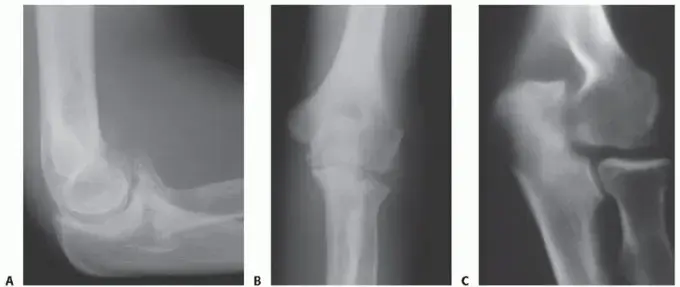

* الرنين المغناطيسي (MRI): يُعد الأداة الأكثر فعالية لتصوير الأنسجة الرخوة مثل الغشاء الزليلي، ويظهر بوضوح مدى تضخمه والتهابه، وأي تلف في الغضاريف أو الأربطة.